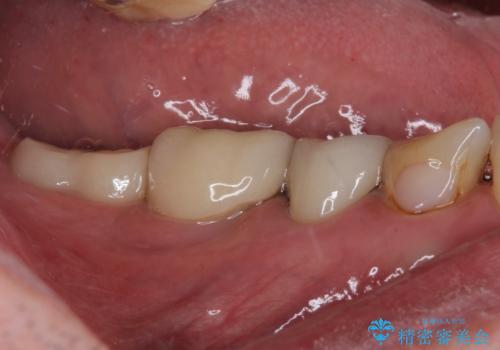

歯肉が退縮したことで見えていた歯根もセラミッククラウンで覆うことができ、清掃性も改善されました。